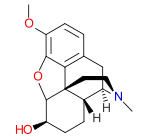

Morphinones and morphols

- 14-Cinnamoyloxycodeinone

- 14-Ethoxymetopon

- 14-Methoxymetopon

- 14-Phenylpropoxymetopon

- 3-Acetyloxymorphone

- 3,14-Diacetyloxymorphone

- 7-Spiroindanyloxymorphone

- 8,14-Dihydroxydihydromorphinone

- Acetylcodone

- Acetylmorphone

- α-hydrocodol (=dihydrocodeine, )

- Benzhydrocodone

- Bromoisopropropyldihydromorphinone cas?

- Codeinone

- Codoxime

- Conorfone (codorphone)

- IBNtxA

- Thebacon (acetyldihydrocodeinone, dihydrocodeinone enol acetate)

- Hydrocodone

- Hydromorphone

- Hydroxycodeine

- Metopon (=methyldihydromorphinone)

- Morphenol

- Morphinone

- Morphol

- N-Phenethyl-14-ethoxymetopon

- Noroxymorphone

- Oxycodone

- Oxymorphol

- Oxymorphone

- Pentamorphone

- Semorphone

Structures